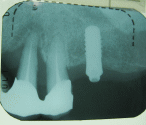

歯根の治療例

症例 1~5は、いずれも歯根の治療を施した結果、綺麗に骨が再生された事例です。